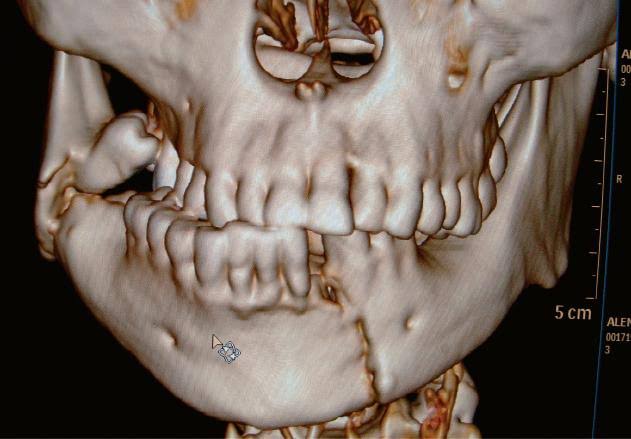

Dental Implants

Dental implants are a long-term solution to tooth loss, providing a natural-looking smile and restoring proper mouth function. Our expert team ensures precise placement and comfortable recovery.